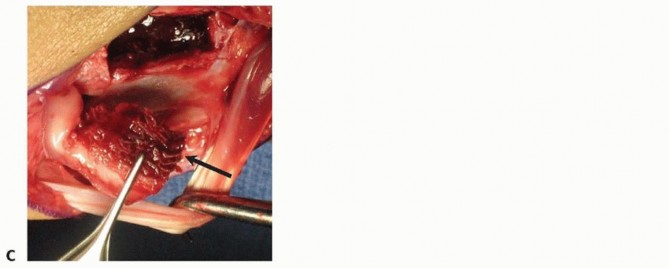

B. Kirschner wire placement is percutaneous, from distal to proximal. The 1,2 IC SRA is not dissected free; rather, it is left as part of the retinacular septum.The tourniquet is deflated, and perfusion of the vascularized bone graft is evaluated (TECH FIG 2C).

TECH FIG 4 • A. The palmar distal radius graft is harvested through the distal portion of the Henry approach to the distal forearm. B. The palmar carpal artery is exposed distal to superficial aponeurosis of the pronator quadratus.(continued)

TECH FIG 4 •(continued)C. The scaphoid nonunion site (at tip of Freer elevator) is débrided to remove fibrous tissue. D. The palmar corticocancellous graft (in forceps) is rotated into the nonunion site. E. The graft is press-fit into the nonunion site and secured with internal fixation.

Periosteum on either side of the palmar carpal artery is incised, and the artery is gently mobilized laterallyto the radial artery.Bone graft harvest from the ulnar half of the distal radius is initiated by periosteal incision with a scalpel, followed by osteotomy and elevation with small osteotomes.Incision through the radioscaphocapitate ligament exposes the scaphoid nonunion site and allow for removal of fibrous tissue (TECH FIG 4C).